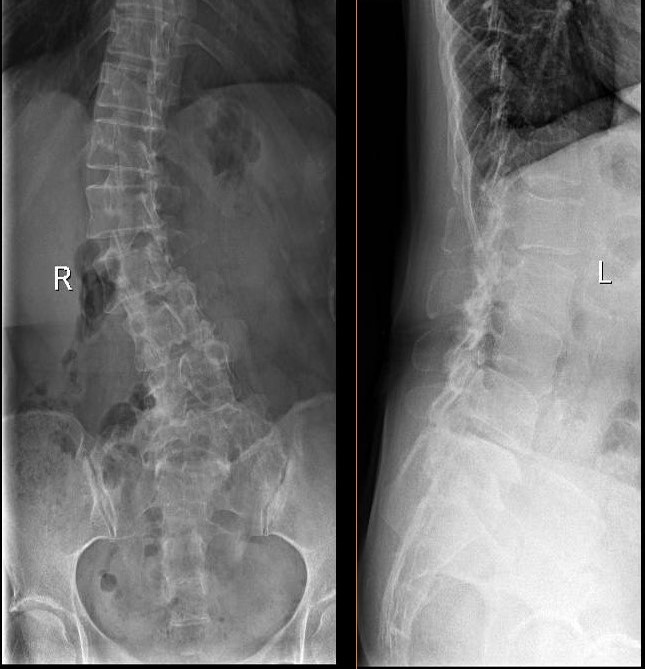

退变性脊柱侧凸(DS)是一种特殊类型的脊柱侧弯,是指成年以后才发生的脊柱侧凸性病变,这类侧凸多发生在腰椎,为非对称性迟变的结果,是继发于椎间盘及椎间关节退变的成人脊柱侧凸,而不是其原有侧凸的进展。DS具有明显的腰痛及根性疼痛症状、病理改变复杂、影像学表现多样。近年来,对于该病的诊疗报道日渐增多,但该病的命名仍未规范,其治疗方法更存在较大争议。

DS的病理变化不同于特发性脊柱侧凸,椎间盘退变是引起腰椎退变性疾病的病理基础。椎间盘退变导致关节突关节退变、增生,关节结构异常;椎间关节制约和稳定功能丧失,出现节段性不稳定。椎间盘退变为初始因素,椎间盘发生磨损、撕裂,椎间隙高度丢失,导致脊柱前、后纵韧带丧失支持和稳定作用,关节突关节面严重破坏。退变性侧凸可以发生在胸腰任何节段,但以腰椎更为多见。

根据患者不同的临床表现和疾病的严重程度,退行性脊柱侧弯的治疗可分为保守治疗和外科手术治疗。因其多伴有多节段严重的椎管狭窄及椎间盘突出,且既有常见的矢状面腰椎滑脱或失稳,又有冠状面上的腰椎侧方滑脱和水平面上的旋转性半脱位,治疗上较单纯的腰椎退变性疾病要复杂。